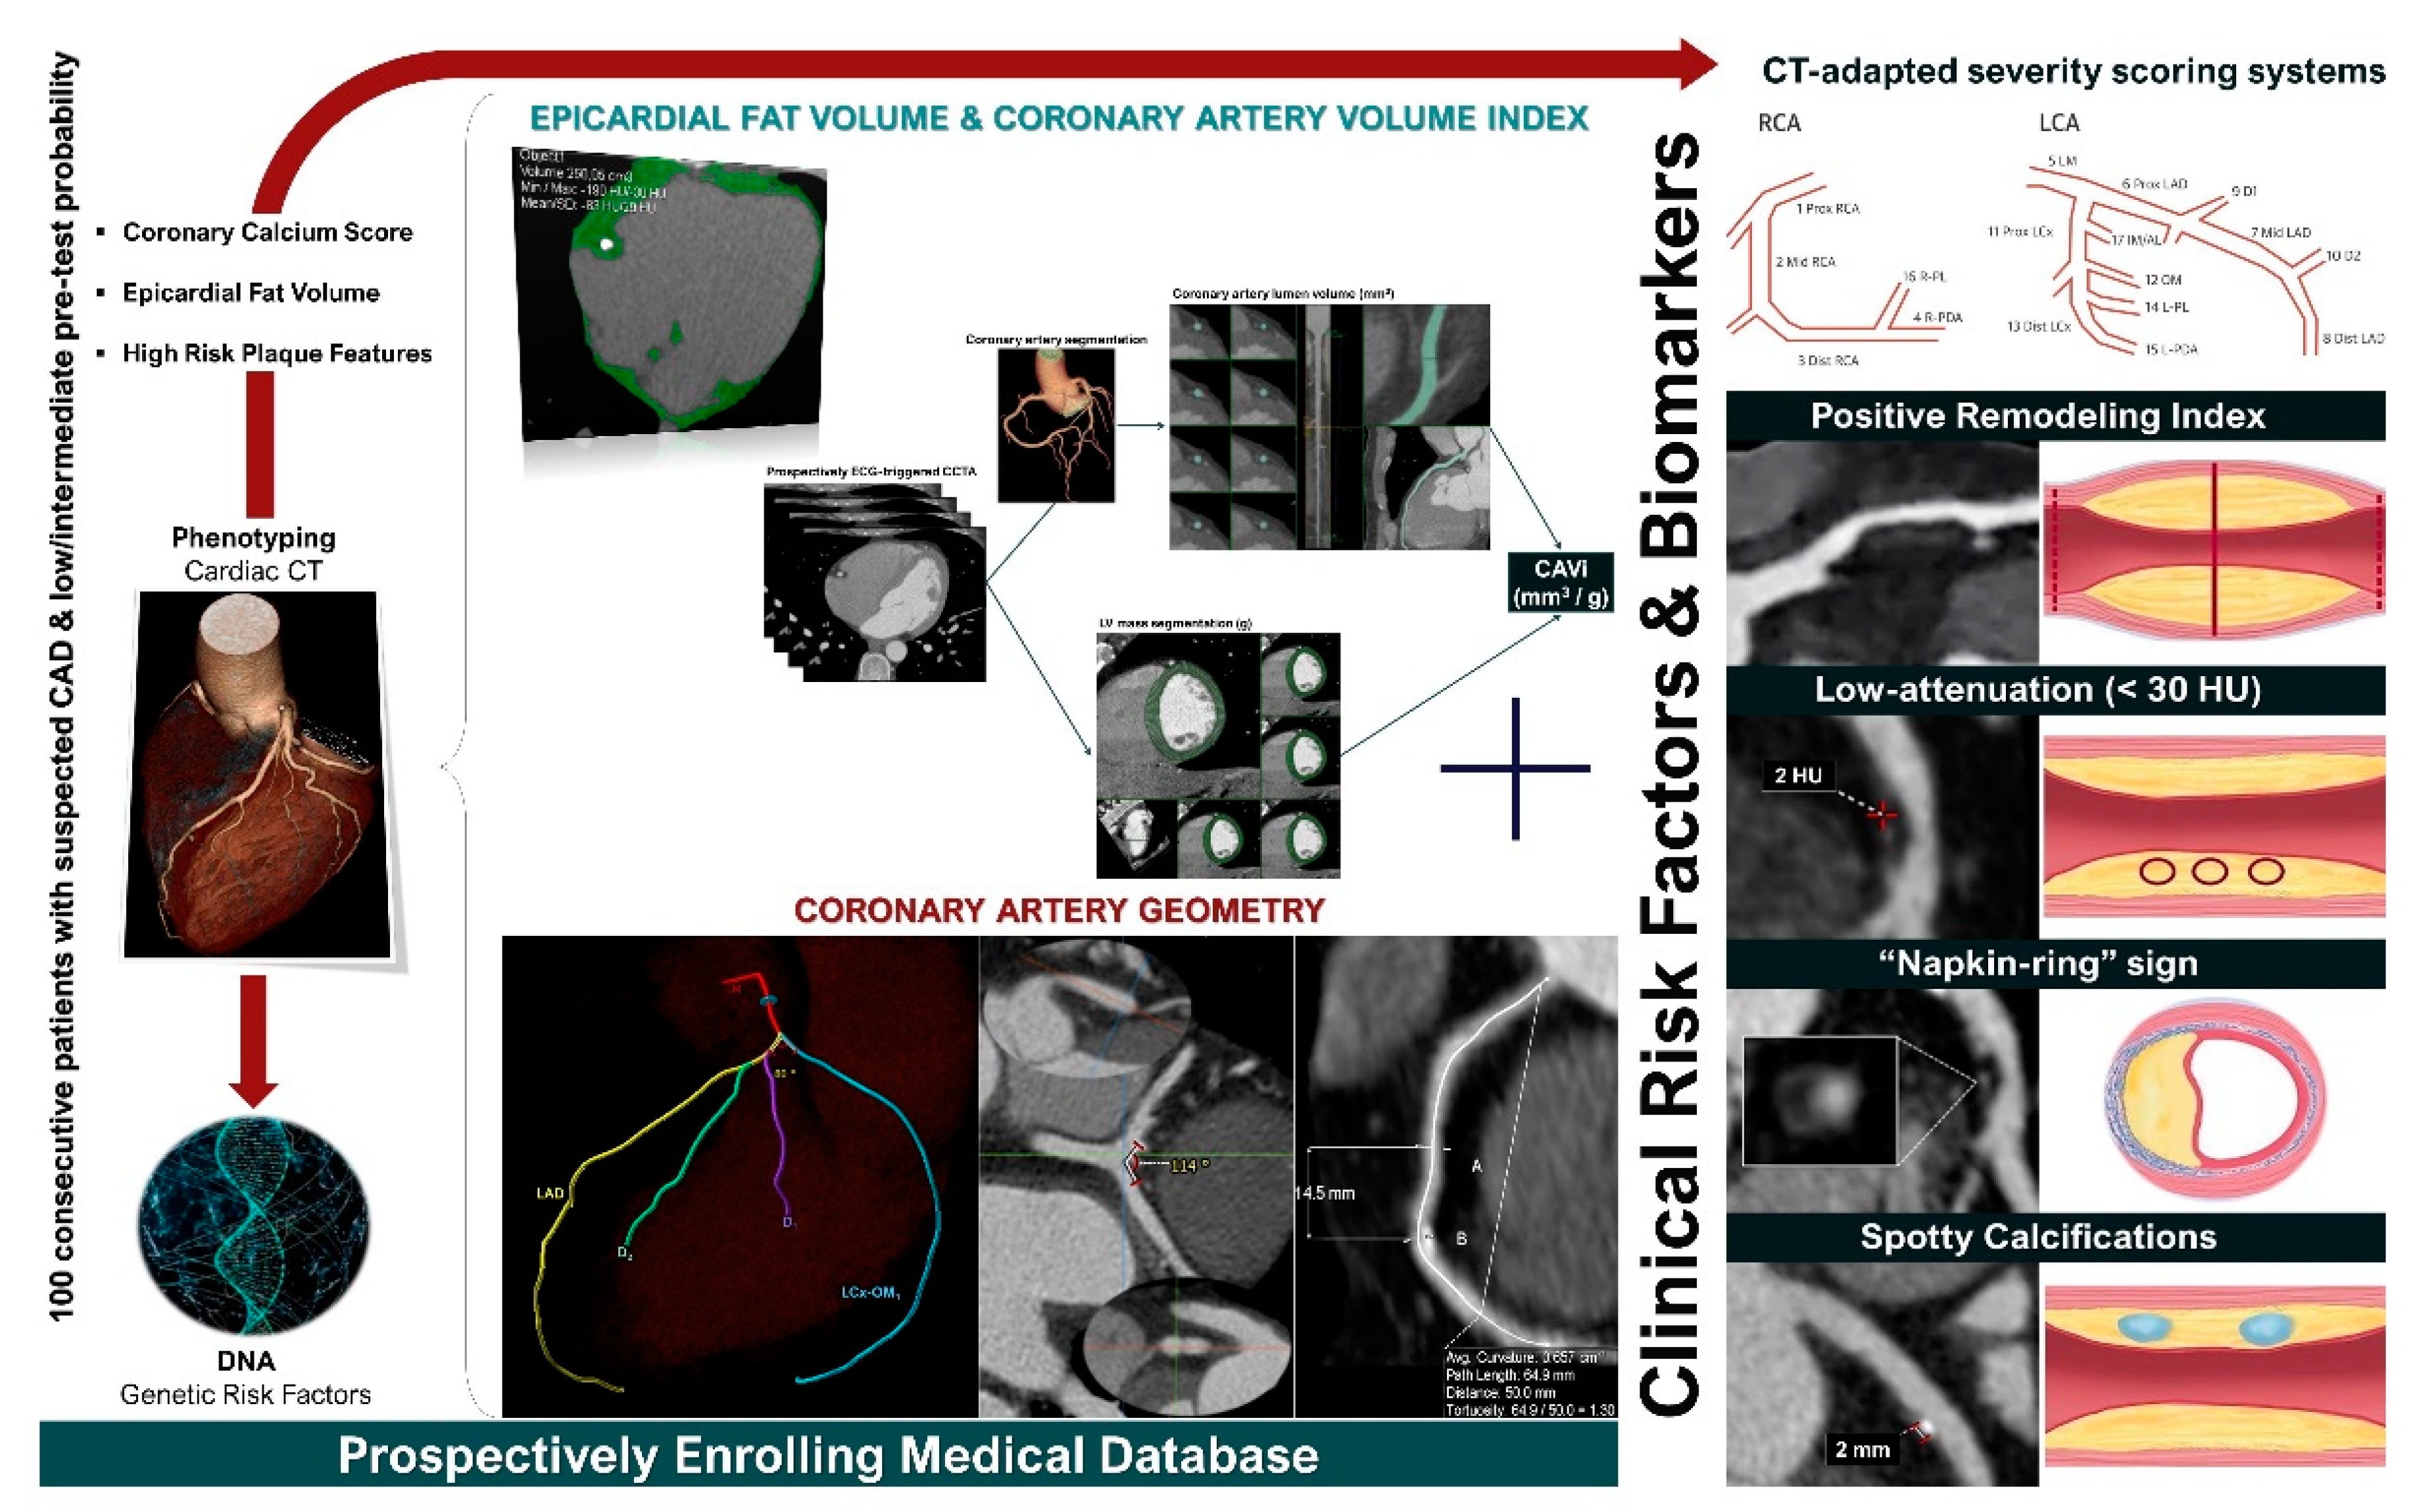

Finally, the ongoing GEOMETRY-CTA study [40] aims to introduce a quantitative, non-invasive imaging biomarker utilizing coronary artery geometric features, clinical and genetic risk factors, serum biomarkers, epicardial fat volume, and the coronary artery calcium score (CACS), to predict the presence and the complexity of CAD on CCTA and investigate its prognostic value regarding adverse cardiovascular events (Figure 2). The study intends to recruit 100 consecutive patients with suspected CAD and low/intermediate pre-test probability. Coronary geometrical characteristics such as the angulation of coronary bifurcations, tortuosity, CAVi [38], and vessel-length will be assessed with multi-planar reformation and volume rendering techniques (Figure 3) and integrated into a single geometric risk score. The extent and vulnerability of plaque burden will be calculated using several anatomical scoring systems such as the Leiden CTA risk score [41] and CT-adapted Gensini score [42]. Patients will be prospectively followed for 12 months after enrollment. In clinical practice, the utilization of such an approach could improve risk stratification and help guide downstream personalized management. Furthermore, the derived index will be available for incorporation in larger national prospective studies for further cardiovascular risk stratification.

Figure 2. GEOMETRY-CTA study design (ClinicalTrials.gov ID: NCT04185493).